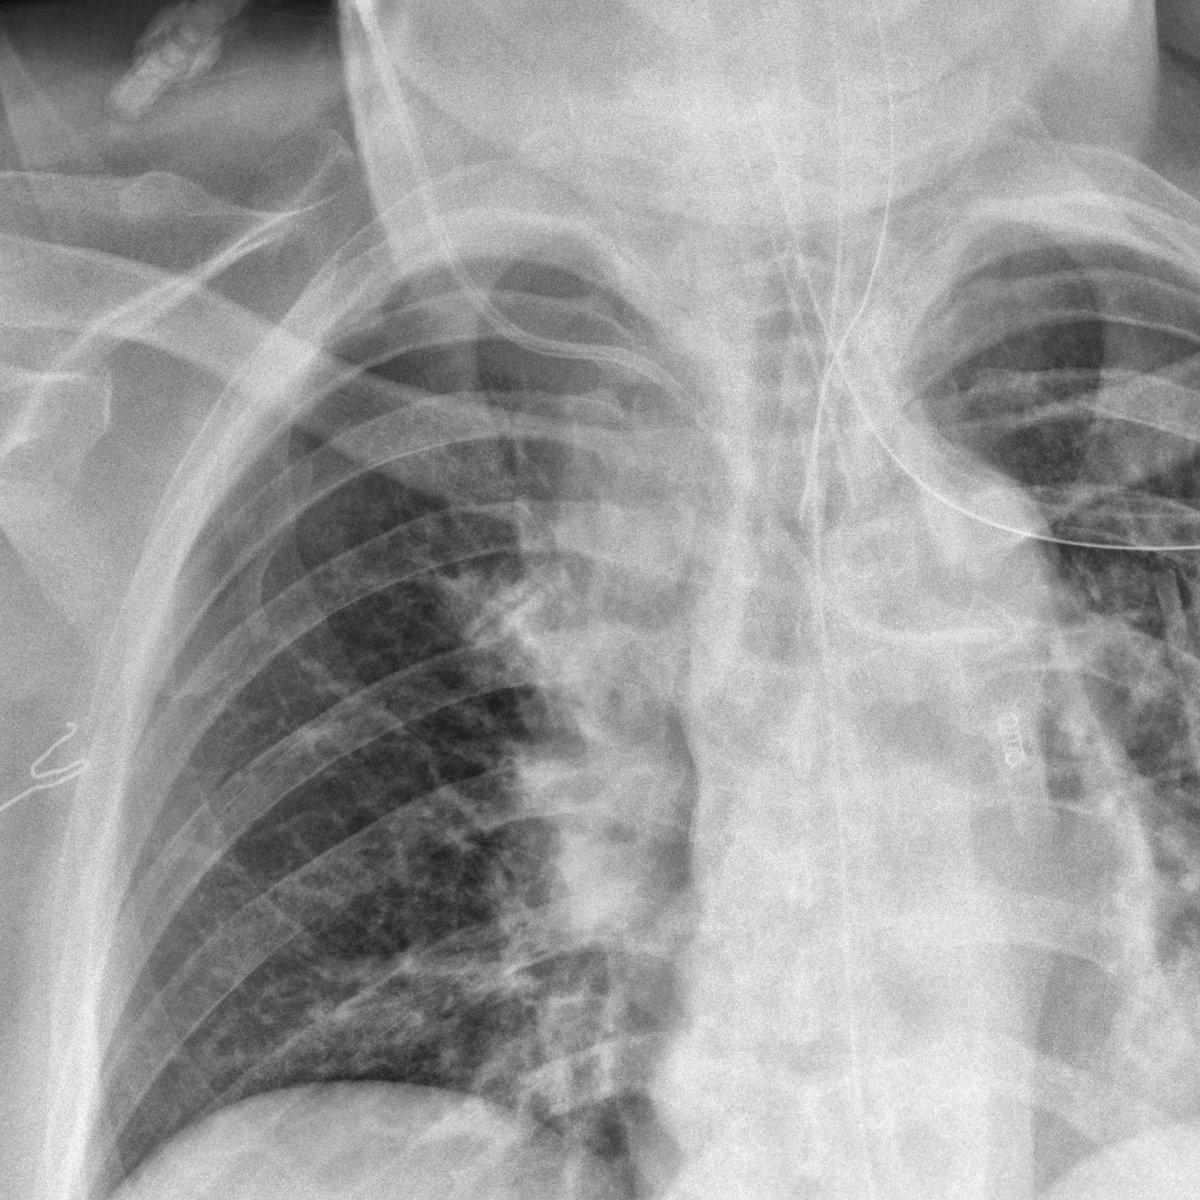

When it rains, it pours.

#radres, 2 complications to placement of the R central venous catheter on this XR... arterial placement AND pneumothorax. Satisfaction of search!#FOAMed#FOAMRadpic.twitter.com/wl1qBZIEbp